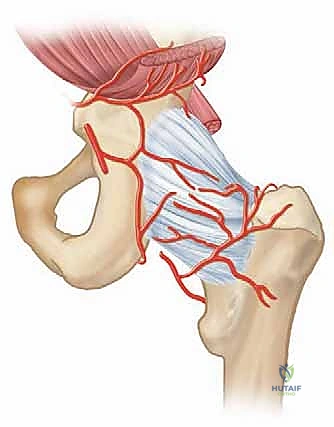

Miniarthrotomy Ankle Arthrodesis: A Masterclass in Surgical Technique and Intraoperative Excellence

Join our masterclass on miniarthrotomy ankle arthrodesis. We'll meticulously cover patient selection, preoperative planning, precise intraoperative technique, comprehensive anatomical considerations, and essential pearls for achieving successful fusion in end-stage ankle arthritis, minimizing soft tissue disruption. This guide ensures fellows master every critical step.

Welcome, fellows, to the operating theater. Today, we're tackling an ankle arthrodesis using the miniarthrotomy technique – a powerful, minimally invasive approach for end-stage ankle arthritis. This procedure, when executed precisely, offers excellent fusion rates with reduced soft tissue morbidity. Pay close attention, as we'll walk through every critical step, from preoperative planning to the final closure, emphasizing the nuances that define successful outcomes.

The miniarthrotomy technique for ankle arthrodesis was initially described for arthritic ankles without significant deformity, bone defects, or AVN. However, with evolving understanding and technique refinement, its indications have expanded.

The inherent advantage of the miniarthrotomy technique is its minimal soft tissue and periosteal disruption, making it particularly well-suited for patients with some of these more challenging conditions, where larger exposures might compromise healing.